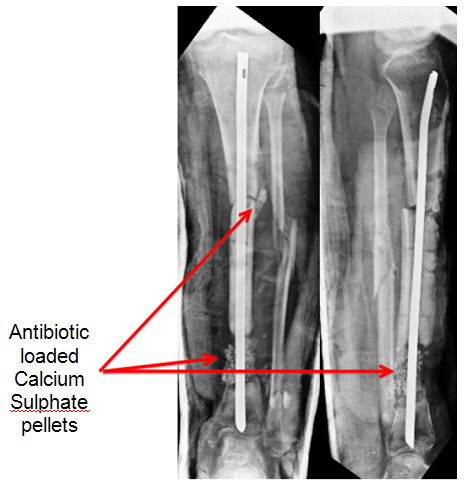

In May 2011, we did the surgery for her and the plan was to do a thorough debridement, use local antibiotic in Calcium Sulphate pellets (Stimulan), and stabilise.

The debridement and the antibiotic pellets was the 'easy' part. How to stabilise a large defect (for I was pretty sure that was what we were going to have at the end of debridement.

Also, having had a fair amount of experience with the TENS nail, I was certain of a reasonable stability as long as the right size and right length (to seat it well upto subchondral bone) was used.

We put in the nails and took care to seat the ends as close to the subchondral bone as we could, thereby gaining some rotational stability. At the lower end of the radius, I buried the end into the bone to provide some resistance against collapse.

Surprisingly (maybe not so surprisingly), with the nails in the forearm was quite stable, to rotation and also preventing collapse of the gap.

We filled in the empty space with Stimulan loaded with 2 gms vancomycin and 3 million units Colistin (based on the earlier culture reports) and sent off tissue samples from multiple areas in the wound for culture (which would decide our IV antibiotics.

| Stabiised by TENS nail. Stimulan Pellets for local Antibiotic Delivery |

The TENS nails did their job of stabilisation well, and xrays showed gradual disappearance of the pellets (as expected).

| Pellets Dissapear over time. TENS nail holds position well |